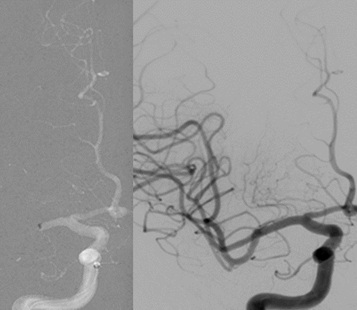

Erste Schlaganfall-Thrombektomie erfolgreich am Klinikum Aschaffenburg durchgeführt

10. Februar 2023 - Am Klinikum Aschaffenburg wurde erfolgreich die erste Thrombektomie bei einem akuten Schlaganfallpatienten durchgeführt. Der Eingriff wurde von Chefarzt PD Dr. Volker Maus durchgeführt und markiert einen wichtigen Meilenstein in der akuten Schlaganfallversorgung am Haus. Weiterlesen